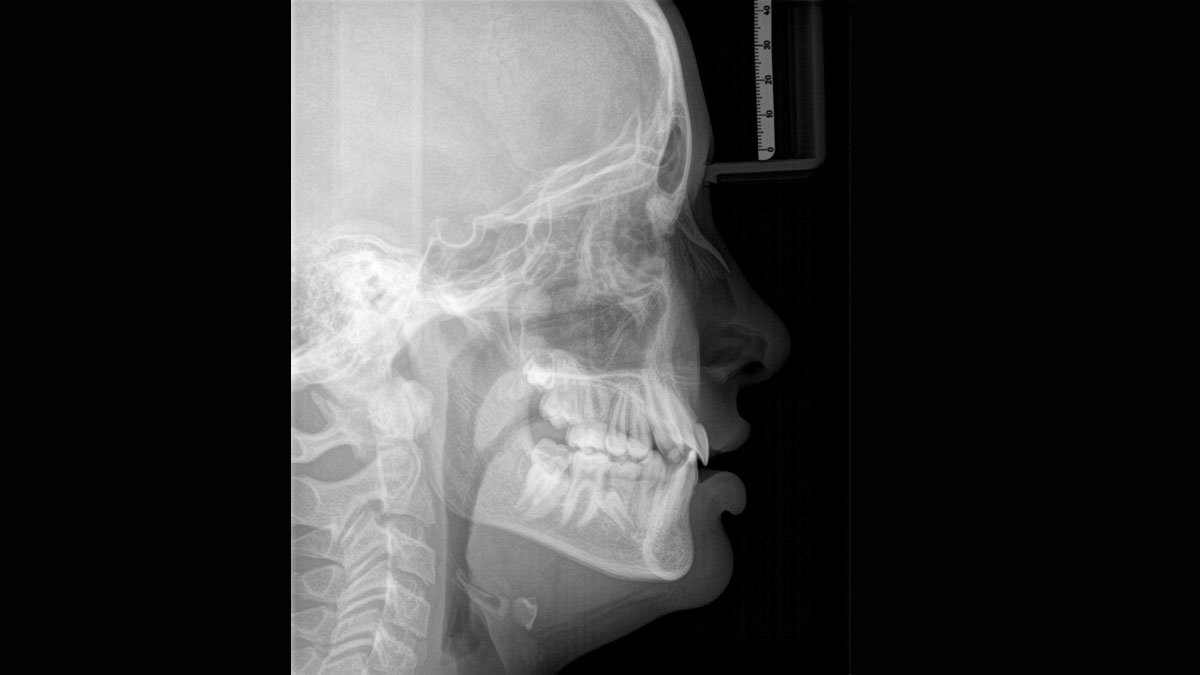

Para obtener imágenes panorámicas excepcionales con alta nitidez. Puede elegir un brazo cefalométrico derecho o izquierdo opcional, que puede reacondicionarse en cualquier momento